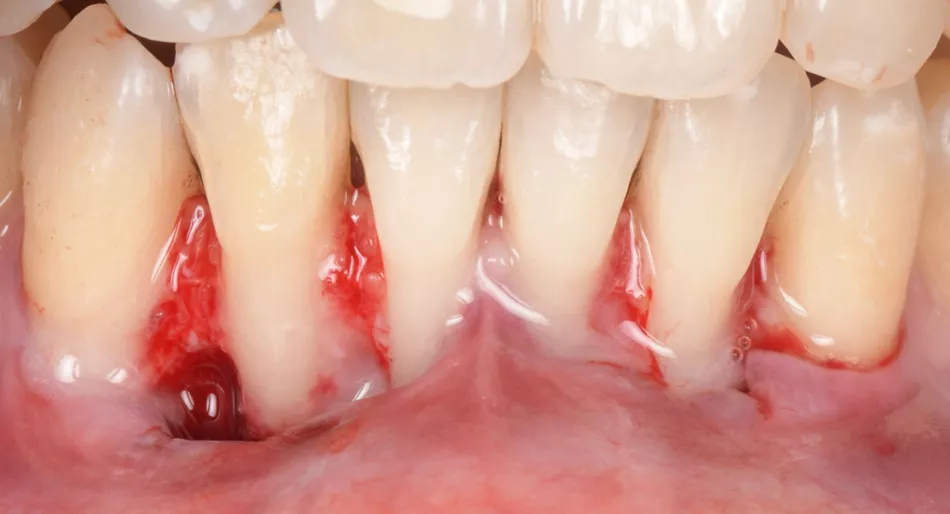

Two split-full-split flaps were raised from teeth #33 to #31 and #41 to #43, with beveled incisions at the base of the papilla (Fig. 3).

Fig. 3